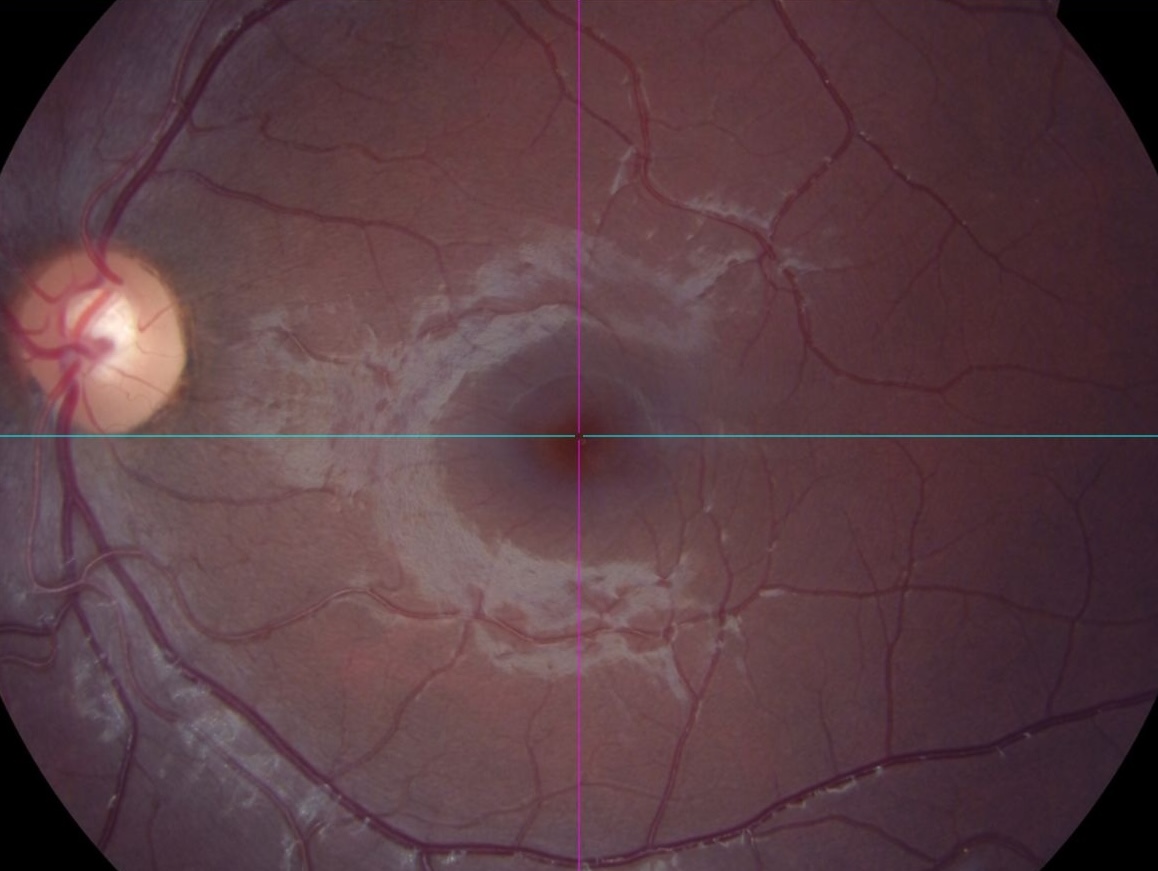

eye see you(stupid joke)—my eye, courtesy of specsavers

help me—again, speaks for itself really.